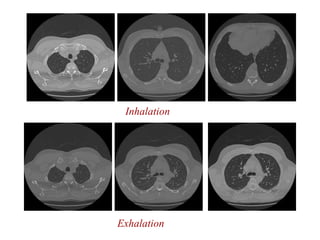

Exhalation

Inhalation

Computerized Tomography (CT),continued Early CT Image Current technology